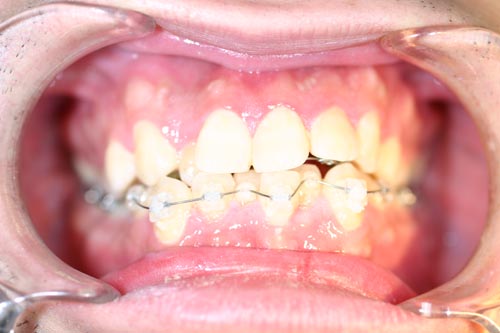

舌側矯正の治療症例

Before

After

上顎前突(出っ歯)を見えない舌側ブラケットによる矯正法で4番の歯を4本抜歯して治した症例

年齢 20代

治療期間 2年6ヶ月

治療費用 1,300,000円

治療のリスク 特になし